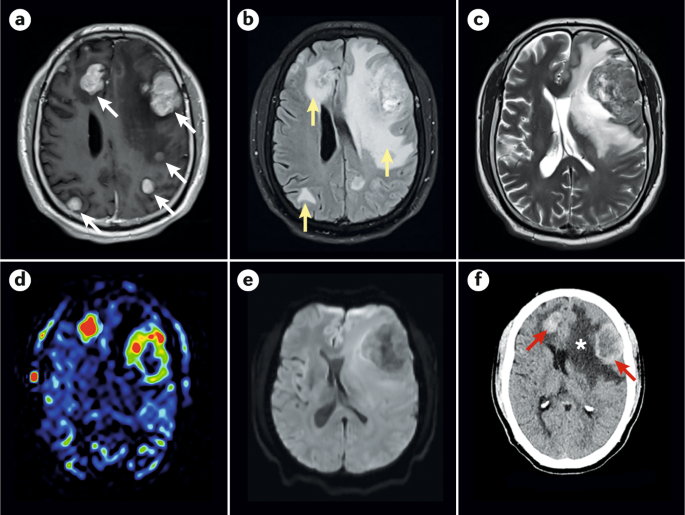

تصویربرداری مغزی

از مهمترین ابزارهای تشخیص متاستاز مغزی، تصویربرداریهای مغزی مانند MRI و CT اسکن است. این تصاویر به پزشکان کمک میکنند تا وجود تومورها در مغز را شناسایی کرده و اندازه و موقعیت آنها را بررسی کنند.

پت اسکن (PET Scan)

پت اسکن یکی دیگر از روشهای تصویربرداری است که به پزشکان کمک میکند تا فعالیت متابولیکی سلولها را در بدن بررسی کنند و محل متاستازهای احتمالی را شناسایی کنند.